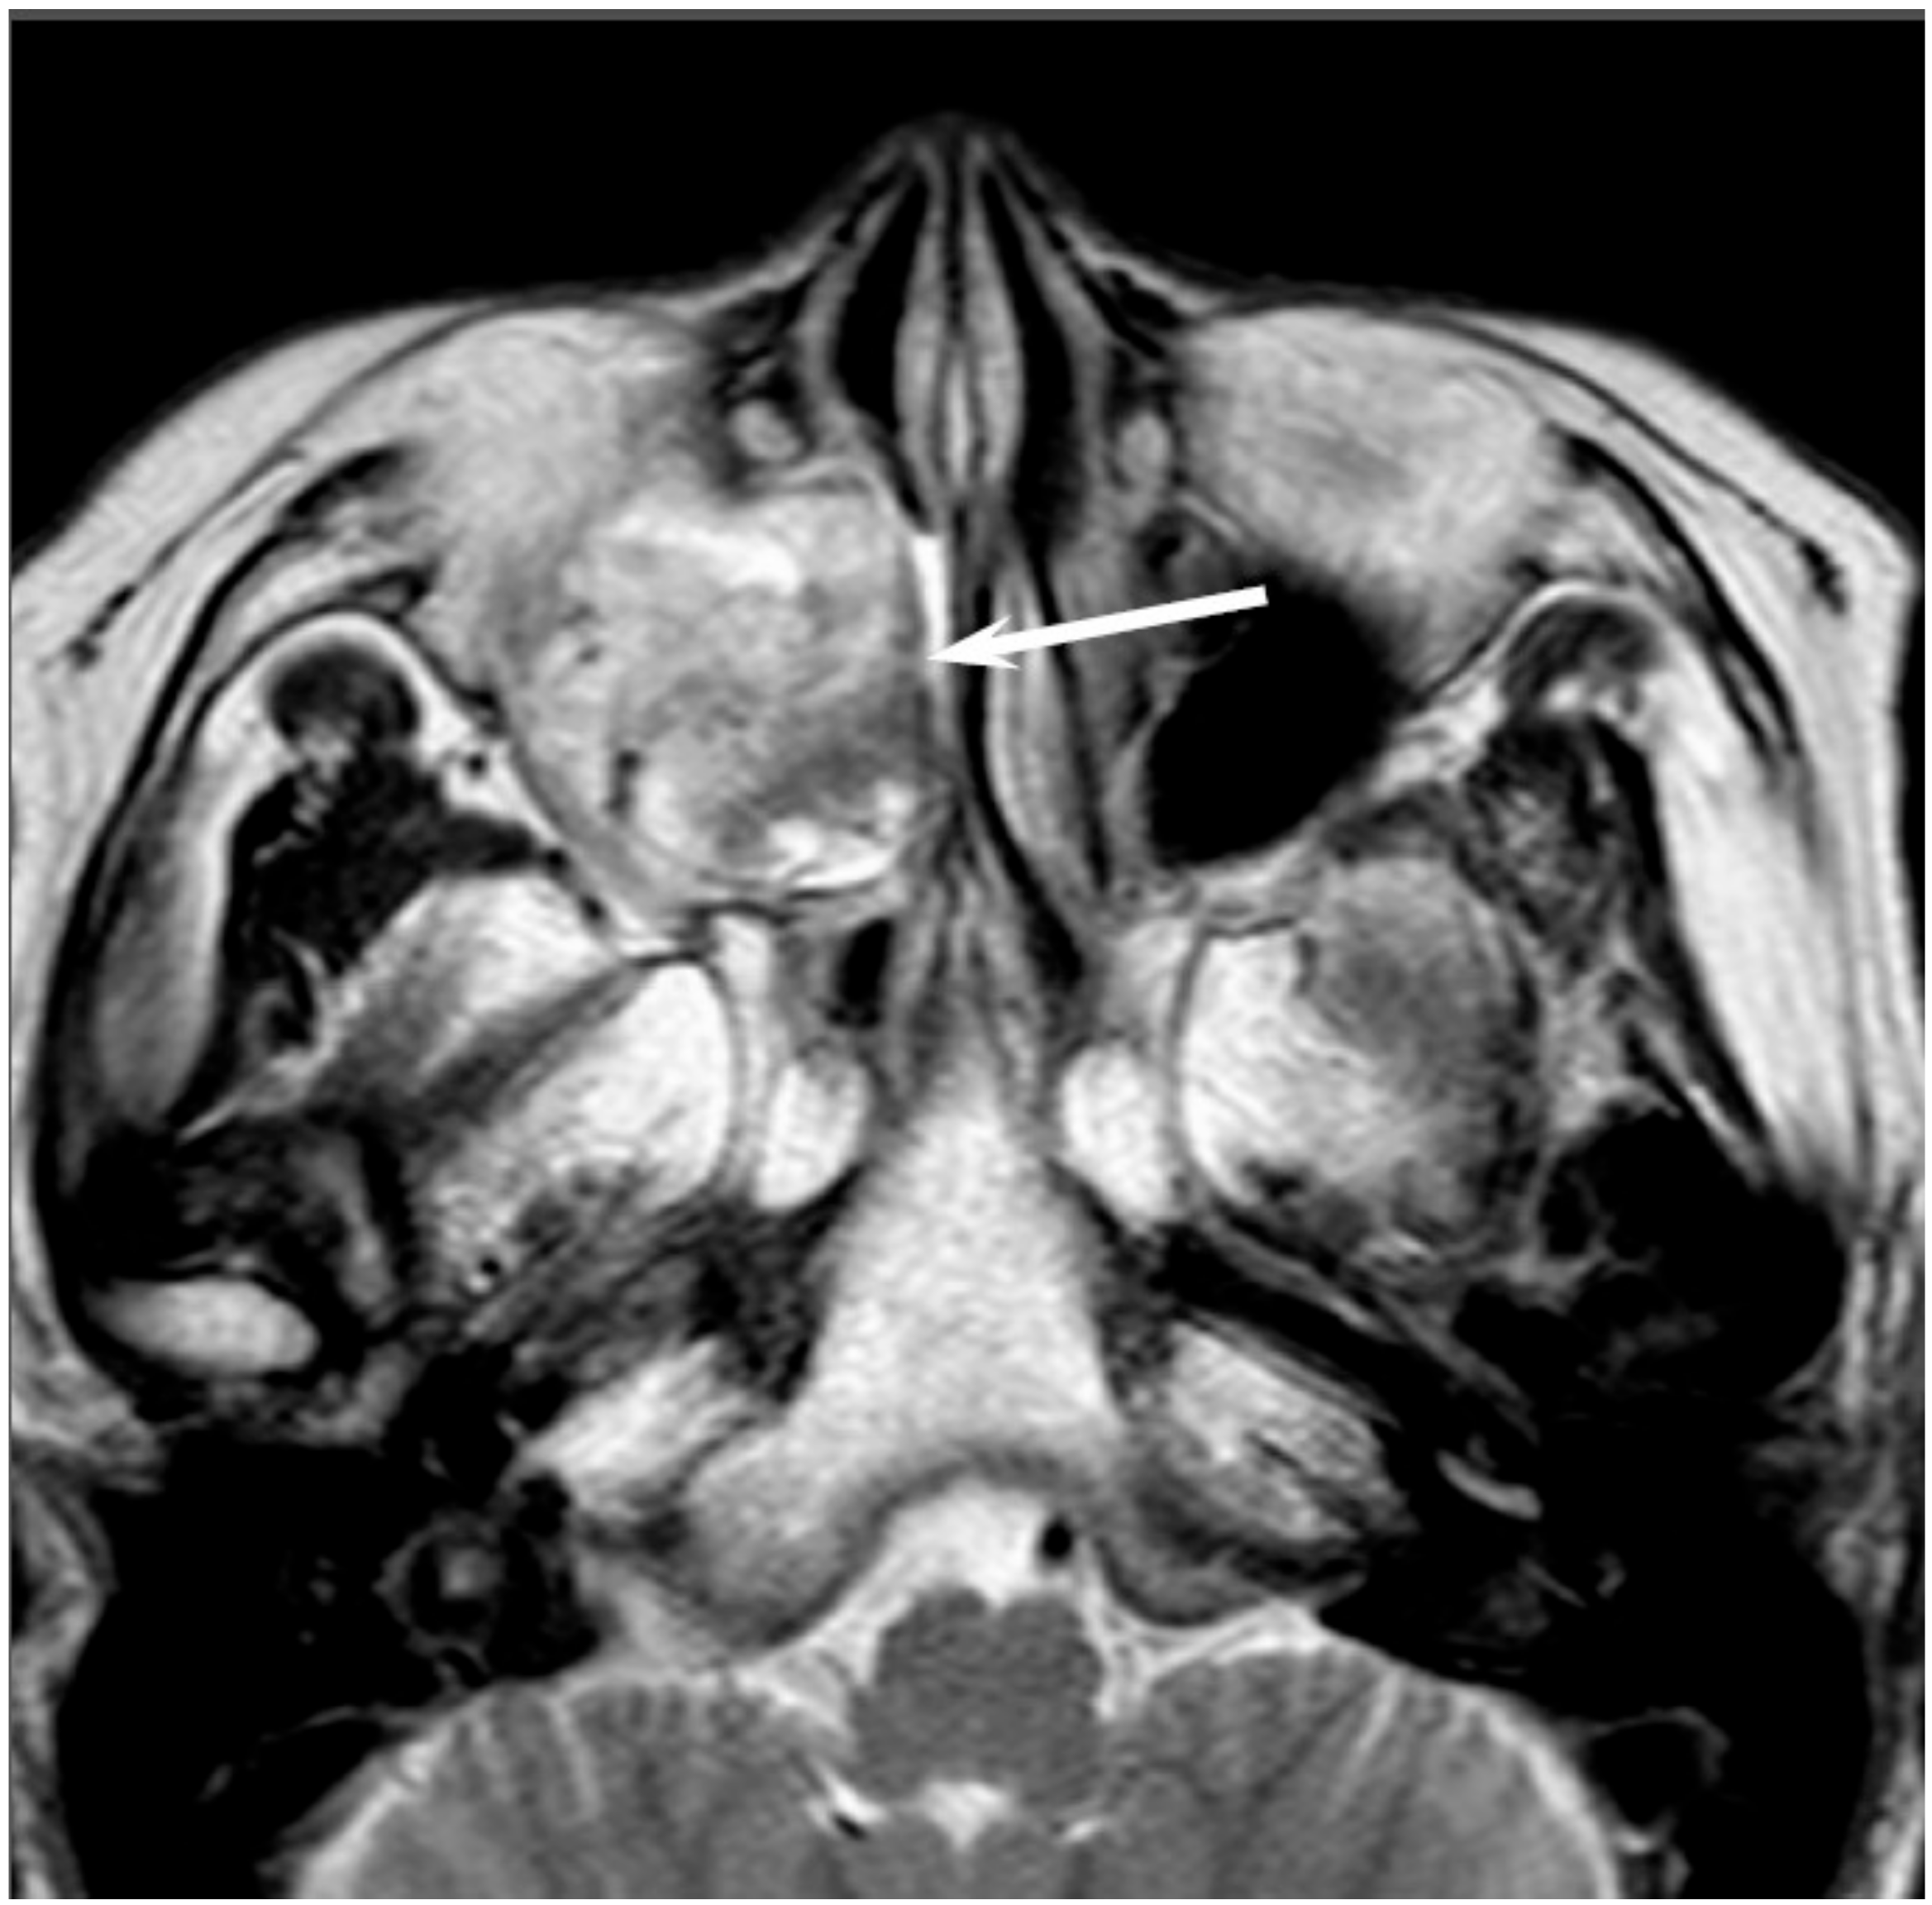

On CT, sinonasal lymphomas frequently show both infiltrative or permeative bony invasion and exhibit varying degrees of regional bony destruction [12]. NHLs with permeative-type tumor invasion typically cross the sinus wall and exhibit remnants of sinus wall as a linear structure within the tumor (Figure 5) [24]. In contrast, bony resorption or remodeling caused by the lymphoma may also be accompanied by bone sclerosis [25]. NHLs usually show isointensity on T1WI and slightly hyperintensity on T2WI [11]. Although the signal intensity of NHLs is nonspecific, the ADC measurement helps differentiate these tumors from other malignancies. In the maxillary sinus, the ADC values of NHL (0.61 × 10−3 mm2/s) were shown to be lower than those of SCCs (0.95 × 10−3 mm2/s), which reflects the greater cellularity of NHLs [12]. Although NHLs usually appear as a homogeneously enhanced mass, necrotic areas within the tumor are occasionally observed in NK/T-cell lymphoma [26,27].

Figure 5. Diffuse large B-cell lymphoma of the left maxillary sinus. Contrast-enhanced CT image showing a homogeneously enhanced lesion accompanied by remaining sinus walls as a linear structure within the tumor (arrows).